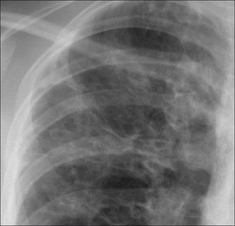

image

Figure 30.6 Mild haemoptysis. Due to infection. Lobar pneumonia.